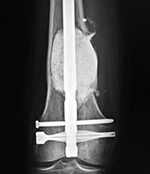

The antibiotic laden cement beads were placed in an area of infected bone after an open fracture. A periarticular locking plate is in the distal femur, and a buttress plate and interfragmentary screws are in the tibia.